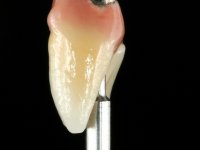

With the implant osteo-integrated with did an impression (open-tray technique) and the dental technician started the construction of a gold framework. The use of an abutment made of a gold alloy allowed us to do a framework with a perfect fit.

During the framework try-in, the color survey was done in order to proceed with the ceramics placement, with a crown and gingiva-components.